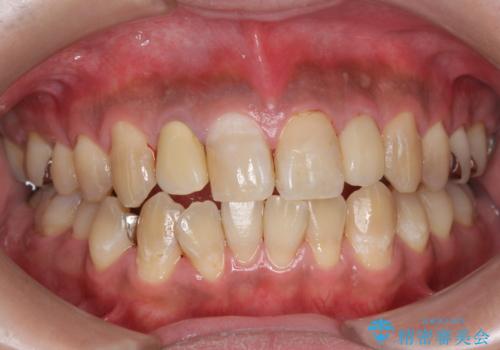

PMTC(歯科医院での専門的クリーニング)でステインを除去し白くきれいな歯に!

PMTC(歯科医院での専門的なクリーニング)

歯の着色だけでなく、汚れも除去し歯の表面がツルツルになったと喜んでいただけました。